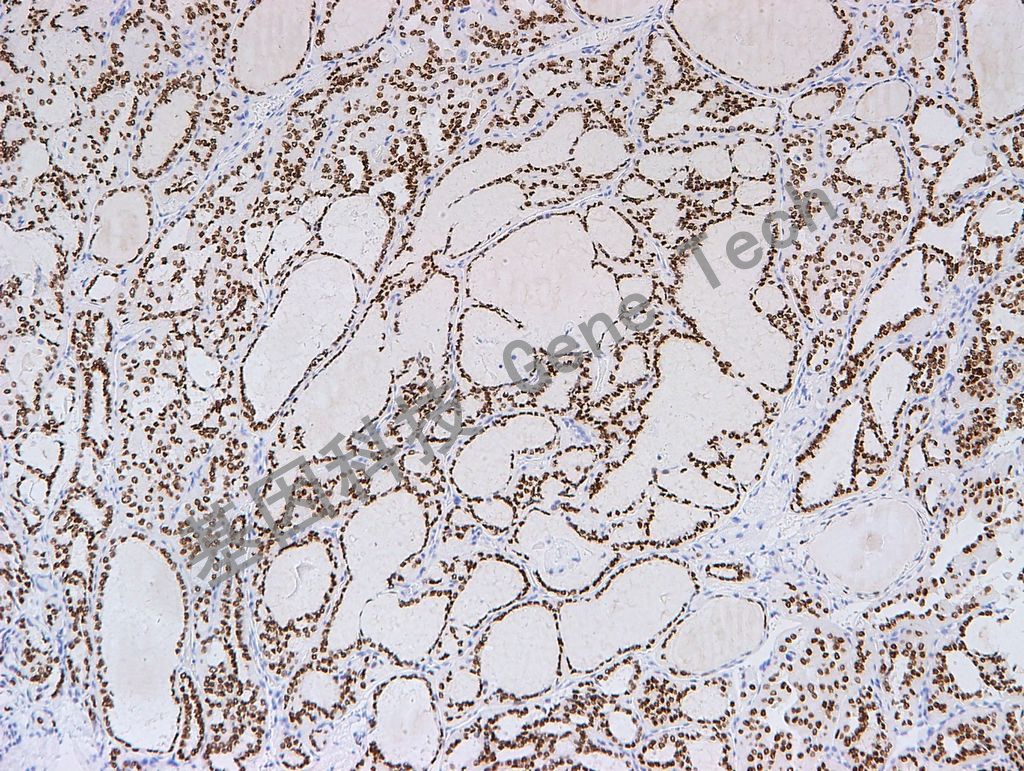

| 預(yù)處理:高pH熱修復(fù) | 陽性部位:細胞核 | 陽性對照:甲狀腺/肺腺癌 |

| 甲狀腺乳頭狀癌石蠟切片,用 TTF-1(GT2180)染色,細胞核陽性,DAB 顯色 | ||